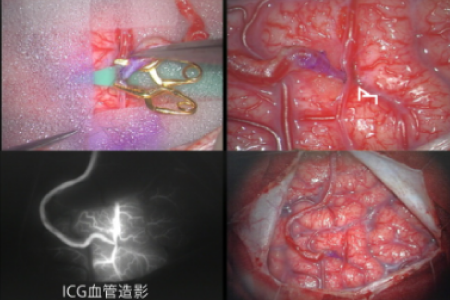

脳動脈瘤、もやもや病などの閉塞性脳血管障害、 脳血管奇形における病態研究を行っています。 特に、若年者の脳卒中の原因として近年増加傾向にある指定難病もやもや病に関しましては 長年の診療経験を踏まえて、遺伝子研究やバイパス周術期病態の解明を中心に先進的研究を推進しています。 もやもや病に対するバイパス手術はガイドラインでも標準治療として推奨されていますが、 術後急性期に局所過灌流(一時的な流れすぎ)や特異な脳虚血病態(watershed shift現象)など、 もやもや病に特徴的な病態を呈することを見出しました。 さらなる治療成績向上を目指して術後急性期の病態解明を脳循環画像やMRIを駆使して推進しています。 また、くも膜下出血の原因として重要な脳動脈瘤に関して高感度MRIを用いた動脈瘤壁イメージング(vessel wall imaging)を 駆使した動脈瘤増大・破裂に関する病態研究を進めています。